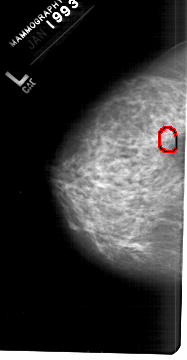

A_1259_1.RIGHT_MLO

RIGHT_CC LINES 5551 PIXELS_PER_LINE 3286 BITS_PER_PIXEL 12 RESOLUTION 43.5 NON_OVERLAY

FILE: A_1259_1.LEFT_CC.OVERLAY

TOTAL_ABNORMALITIES 1

ABNORMALITY 1

LESION_TYPE CALCIFICATION TYPE PLEOMORPHIC DISTRIBUTION CLUSTERED

ASSESSMENT 4

SUBTLETY 2

PATHOLOGY BENIGN

TOTAL_OUTLINES 1

BOUNDARY